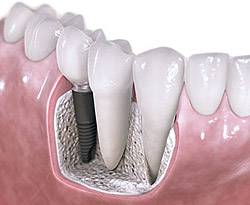

İmplant kaybedilen diş kökünün yerine çene kemiğine yerleştirilen, titanyum malzemesinden üretilmiş küçük bir parçadır. İmplant ayakta tedavi kapsamında lokal anestezi altında yapılan bir operatif işlemdir. Günümüzde yapay diş kökleri diş hekimleri tarafından hemen hemen her boşluğu doldurmakta kullanılabilmektedir.

İmplantlar güvenilir bir stabilite sunmanın yanısıra yapılacak dişlerinde doğal görünmesini sağlar.

Bir diş boşluğunu doldurmak için implant kullanıldığında komşu dişlere zarar görmeyerek doğal diş yapısının bozulması engellenir.

İmplantlar çiğneme kuvvetlerini çene kemiğine ileterek kemiğin erimeden kalmasına yardımcı olur.